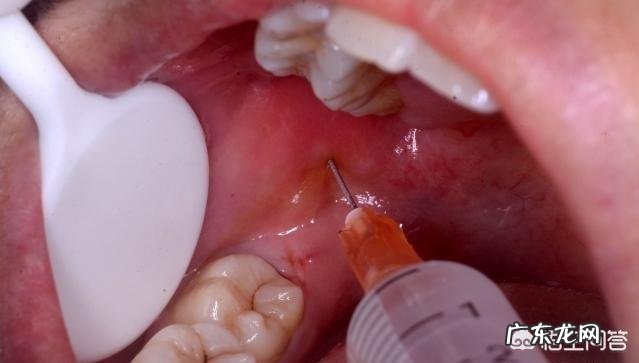

拔牙前,需要先麻醉 。拔牙过程是不疼的 。待麻药效果消失了,会有疼痛不适的感觉,依据牙齿生长的位置等决定的拔牙难度,不适感会有差异 。必要时,可以服用止疼药物,多休息有助于尽早恢复 。祝好[笑]

位置不正的智齿拔出还是很有必要的,否则后患无穷 。拔智齿属于手术,你紧张是很正常的,首先拔牙之前是要签字的,当然你大可不必放大这种紧张感,拔牙之前会进行麻醉,起效后几乎不会感到疼痛,只是那种牙齿用器械剥离时的那种感觉有点不适 。牙齿拔除后,咬棉花半小时,回家后一天内不要刷牙漱口,防止感染引发干槽症,拔牙后几天内尽量吃流食,如果疼痛明显,可以静脉注射消炎药,尽快恢复 。

局麻下拔智齿是不疼的,除非牙龈还有炎症,手术到后期才可能有痛感,或者是拔除难度大,比如贴近神经管的,手术时间已经过了一个多钟,麻醉效果没那么好,普通智齿拔除最快不到10分钟,具体看位置长得怎样,要说痛一般在术后比较明显 。